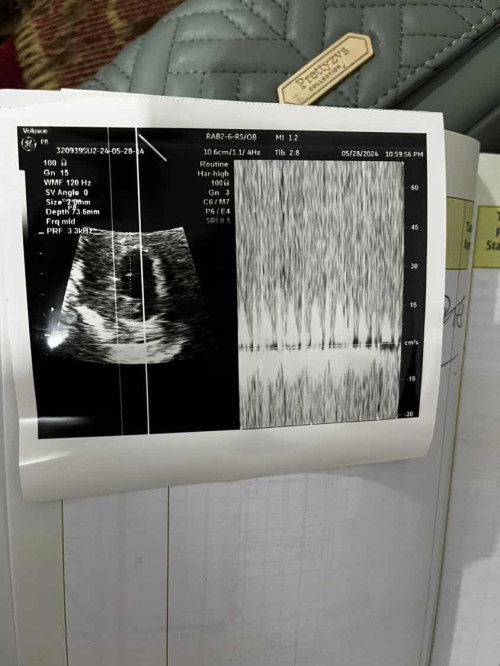

Usg 7week ada yg sama kah bun?

Ini hasil usg kehamilanq yg masih 7minggu bunda Masih kuecil Tp detakjntungnya udaa ada